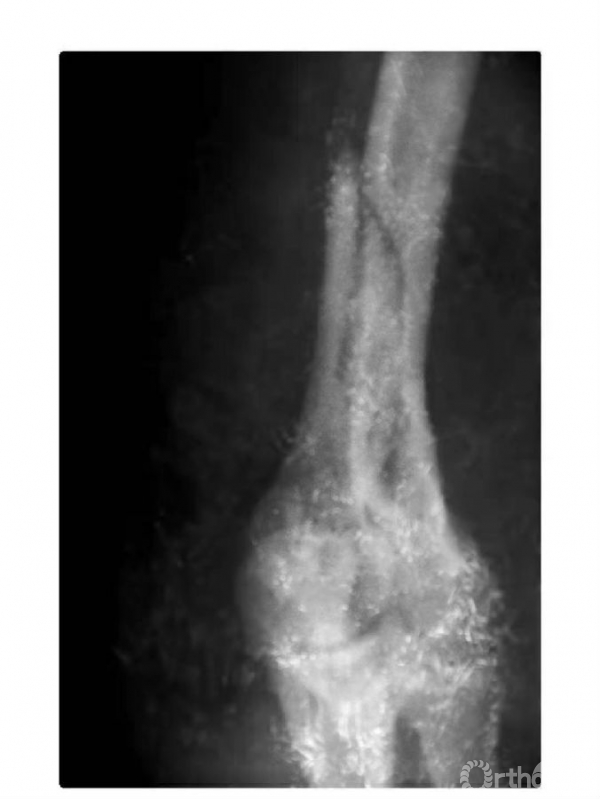

例3:肱骨内髁骨折,骨块向前上移位,并上尺桡关节分离致尺肱关节不稳,且桡骨干近段呈代偿性粗大(图6)。

图6

例5:肱骨内髁外侧壁骨骺因损伤而早闭,而内外侧骨骺继续生长致滑车沟变深,继而肱骨下端形成鱼尾状畸形(图8)。

图8